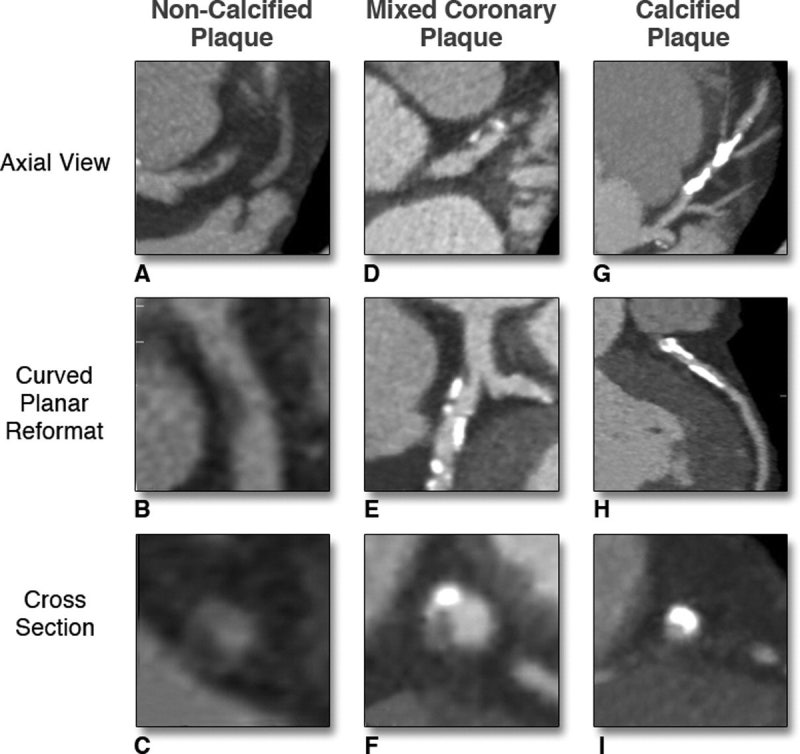

스타틴의 부작용으로는 근육통, 근력 약화, 간 기능 장애, 인지 기능 저하 등이 있으나 실제 임상 경험상 드물고 자가면역 혈관 질환(예: 타우, 동맥염 또는 가와사키병)과 관련이 있는 경우는 드물다. 신장이 제대로 기능하지 않는 경우 지연이나 검사가 필요하지 않을 수 있습니다. 흉통을 인지하고 적절한 치료를 받으면 관상동맥 질환의 위험을 줄일 수 있습니다. 광범위한 손상은 심각한 응급 상황과 만성 심부전으로 이어질 수 있으며, 이는 심장 기능 저하, 고콜레스테롤 및 스타틴 부작용으로 이어집니다. 협심증의 증상은 특히 흉골 전면 바로 아래의 가슴에 압박감, 조임 및 통증이 있습니다. YouTube를 서핑하고 일부를 본 다음 인터넷 검색에 어려움을 겪고 있습니다. 결국 어디 가서 정보를 수집하고 모두가 유명하다는 등 너무 많은 것을 추천합니까? 심장기능, 혈관질환, 석회화, 정도 등을 미리 예측할 수 있습니다. 관상동맥 석회화의 정도는 정상이고 일정 범위를 갖지만 경증, 중증, 중등도 및 고도의 관상동맥 석회화로 나눌 수 있습니다. 손상이 광범위하면 매우 위험한 응급 상황이 될 수 있으며 장기간 반복되면 심부전 및 심장 기능 저하로 이어질 수 있습니다. 수술적 합병증이 있을 수 있으나 심각한 기저질환이 없는 대부분의 환자에게 관상동맥우회술의 위험성은 약물복용 중 안전한 회복과 퇴원이다. 연구팀은 공복혈당과 당화혈색소에 따른 관상동맥석회화 위험도를 발표한 최인영 교수와 장유수 교수의 연구에서 관상동맥 석회화 위험이 1명에서도 증가했다. 당뇨병 이전 수준. 연민 이 상태에 있다면 건강한 생활 방식과 혈압, 혈당 및 콜레스테롤 수치 상승을 방지하는 방법을 실천하십시오. 유투브도 돌아다니고 영상도 보고 웹서핑도 하고. 결국, 모두가 마음으로 정보를 수집하고 유명하든 아니든 너무 많이 추천하고 싶다면 어디로 가야합니까?